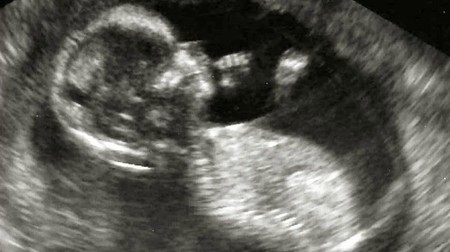

El feto crece rápidamente. A las 14 semanas de embarazo pesará unos 30 gramos y medirá aproximadamente 10 centímetros. Parece un bebé en miniatura.

En la semana 14 de embarazo, la cabeza sigue siendo desproporcionada en relación con el cuerpo, aunque el bebé ya es perfectamente reconocible como un pequeño humano. Sus rasgos faciales van haciéndose cada vez más evidentes y hasta podríamos ver cómo hace gestos con los músculos de su cara, se chupa el dedo y la manita.